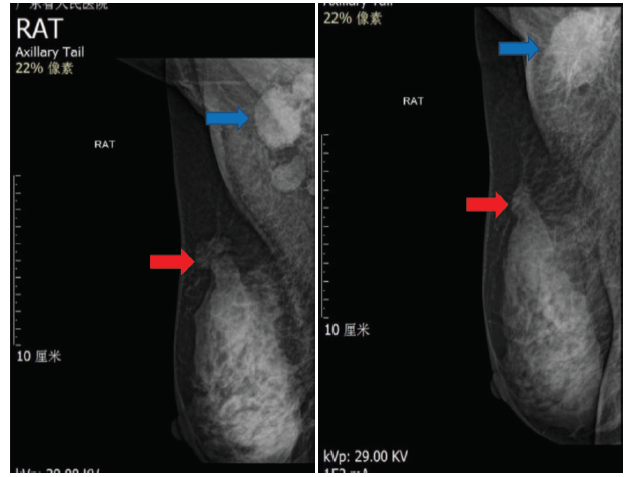

辅助检查:肿瘤指标正常。行乳腺彩超示:右乳10点钟位置距乳头5.0 cm可见一个大小为2.5 cm× 1.7 cm低回声光团, 形态不规则, 边界不清, 呈“ 蟹足样” 改变。右腋窝可见多个淋巴结回声, 边界清, 形态不规则, 皮髓质分界不清, 内回声不均匀, 其中一个淋巴结大小约2.5 cm× 1.9 cm。行乳腺核磁共振示:右乳外上象限乳腺癌伴右侧腋窝淋巴结转移, BI-RADS V类。见图1。行乳腺钼靶示:右乳外上象限恶性病变并右侧腋窝多发淋巴结转移, BI-RADS V类。见图2。行胸部-上腹部CT未见明显转移。